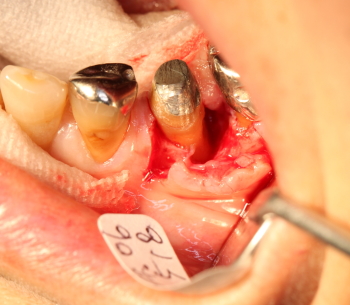

歯槽膿漏による歯ぐきの痛みと骨欠損のケース

35番遠心より排膿

同部を剥離、掻爬